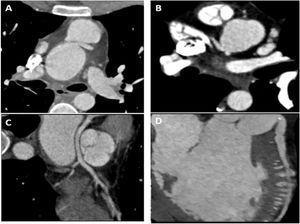

Five (13%) had acute angulation at the coronary origin (Figure 1A): three at the ostium of the left main coronary artery (LMCA); one at the ostium of the right coronary artery (RCA); and one at the ostium of the left anterior descending artery (LAD) which originated directly from the aorta.

Case examples of patients with abnormal coronary findings on computed tomographic coronary angiography. (A) Interarterial course of the left main coronary artery with acute angulation at the ostium. (B) Variant coronary anatomy pattern with both the left main coronary artery and right coronary artery originating from a rightward SOV. (C) Multiplanar reconstruction showing retroaortic course of the left anterior descending artery in a patient with a single coronary artery originating from a rightward sinus of Valsalva. (D) Multiplanar reconstruction of the left anterior descending artery showing intracavitary course into the right ventricle.

Thirteen (33%) patients had variant coronary anatomy patterns: three (8%) patients had a single coronary artery; six (15%) patients had anomalous origin at the sinus of Valsalva (SOV) (Figure 1B); and four (10%) patients had anomalous origin of the circumflex artery (CX) from the RCA.

Interarterial course was described in three (8%) patients – two of the LMCA and one of the RCA. None had evidence of extrinsic compression at rest. Retroaortic course was reported in eight (21%) cases. Of these, six were due to anomalous origin of the CX (four from the RCA, one from a rightward SOV and one from an anterior SOV). One case had a single coronary artery originating from a rightward SOV and the LAD had a retroaortic course (Figure 1C). The other patient had anomalous origin of the LMCA and RCA from a rightward SOV (with both arteries describing a retroaortic course). One patient had anomalous course of the LAD into the right ventricle (Figure 1D), a mild calcified ostial stenosis of the LMCA and chronic total occlusion of the RCA.